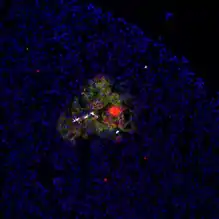

Beta cells (β-cells) are specialized endocrine cells located within the pancreatic islets of Langerhans responsible for the production and release of insulin and amylin.[1] Constituting ~50–70% of cells in human islets, beta cells play a vital role in maintaining blood glucose levels.[2] Problems with beta cells can lead to disorders such as diabetes.[3]

For instance, transcriptomics have allowed researchers to comprehensively analyze gene transcription in beta-cells to look for genes linked to diabetes.[2] A more common mechanism of analyzing cellular function is calcium imaging. Fluorescent dyes bind to calcium and allow in vitro imaging of calcium activity which correlates directly with insulin release.[2][37] A final tool used in beta-cell research are in vivo experiments. Diabetes mellitus can be experimentally induced in vivo for research purposes by streptozotocin[38] or alloxan,[39] which are specifically toxic to beta cells. Mouse and rat models of diabetes also exist including ob/ob and db/db mice which are a type 2 diabetes model, and non-obese diabetic mice (NOD) which are a model for type 1 diabetes.[40]